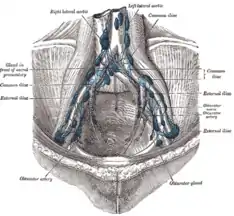

Blood and lymphatic vessels

The prostate receives blood through the inferior vesical artery, internal pudendal artery, and middle rectal arteries. These vessels enter the prostate on its outer posterior surface where it meets the bladder, and travel forward to the apex of the prostate.[3] Both the inferior vesicle and the middle rectal arteries often arise together directly from the internal iliac arteries. On entering the bladder, the inferior vesical artery splits into a urethral branch, supplying the urethral prostate; and a capsular branch, which travels around the capsule and has smaller branches which perforate into the prostate.[3]

The veins of the prostate form a network – the prostatic venous plexus, primarily around its front and outer surface.[3] This network also receives blood from the deep dorsal vein of the penis, and is connected via branches to the vesical plexus and internal pudendal veins.[3] Veins drain into the vesical and then internal iliac veins.[3]

The lymphatic drainage of the prostate depends on the positioning of the area. Vessels surrounding the vas deferens, some of the vessels in the seminal vesicle, and a vessel from the posterior surface of the prostate drain into the external iliac lymph nodes.[3] Some of the seminal vesicle vessels, prostatic vessels, and vessels from the anterior prostate drain into internal iliac lymph nodes.[3] Vessels of the prostate itself also drain into the obturator and sacral lymph nodes.[3]

Imaging showing the inferior vesical, inferior pudendal and middle rectal arteries arising from the internal iliac arteries.

Imaging showing the inferior vesical, inferior pudendal and middle rectal arteries arising from the internal iliac arteries. Image showing the external iliac lymph nodes and their positions around the external iliac artery and vein

Image showing the external iliac lymph nodes and their positions around the external iliac artery and vein